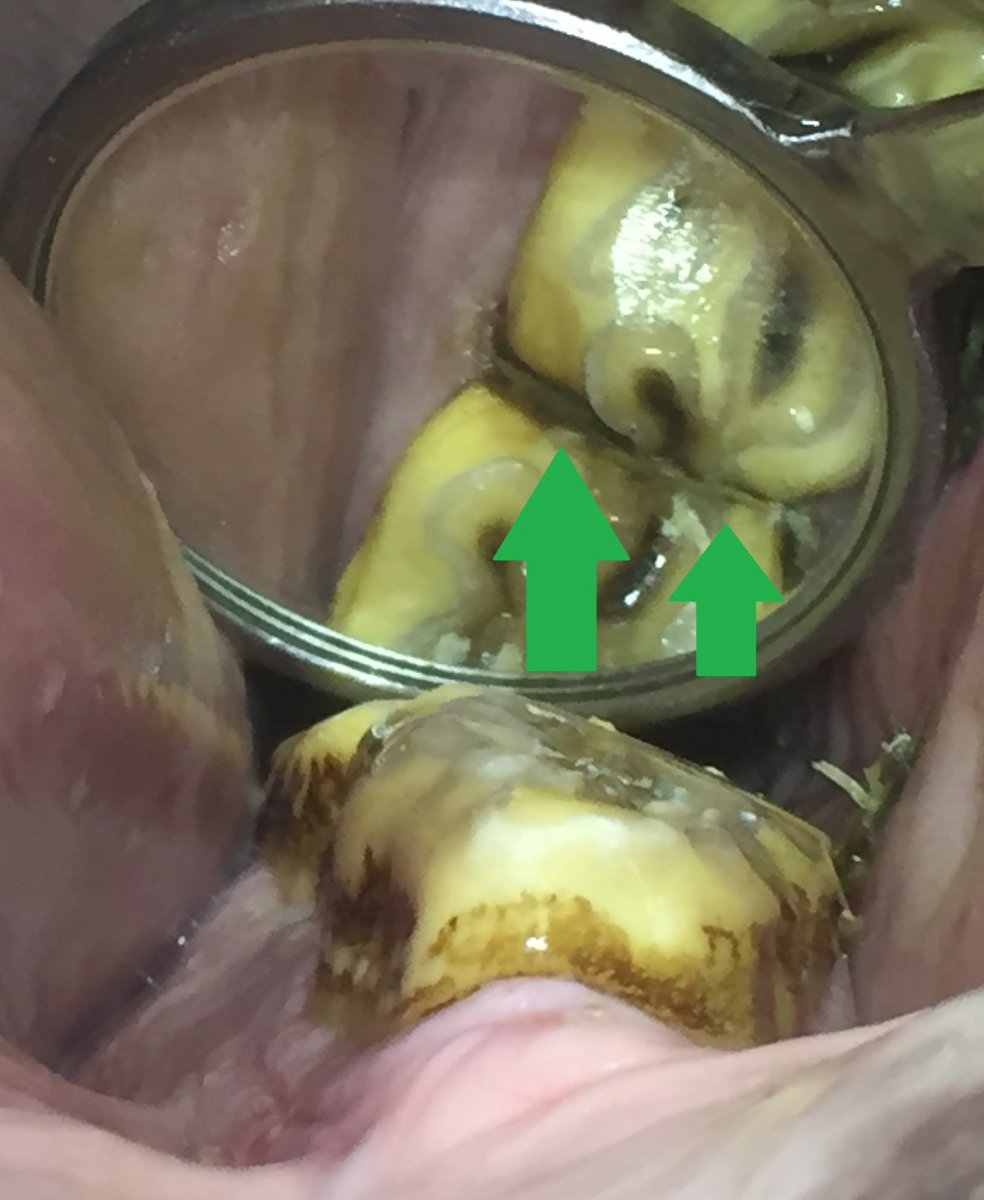

Et diastem er et mellemrum mellem to tænder. Heste kan have to forskellige slags diastemer – valvulære og åbne diastemer. Et valvulært diastem er defineret som et mellemrum mellem to tænder, hvor tænderne slutter tæt sammen ved tyggefladen, men der er mellemrum ved tandkødet. Ved et åbent diastem er mellemrummet lige stort ved tandkød og tyggeflade.

Diastemet vil altid skulle renses, så det fastklemte foder kommer væk og ikke generer tandkødet. Har diastemet været til stede i længere tid, kan den modstående tand være begyndt at vokse ned i mellemrummet. Når hesten tygger sit foder, vil denne tand så være med til yderligere at presse tænderne fra hinanden og foderet ned i mellemrummet. I sådanne tilfælde kan problemet ofte løses ved at slibe noget af den forvoksede tand og dermed mindske den mængde foder, der bliver presset ned i diastemet og trykket på tænderne.

En anden behandlingsmulighed er at lave diastemet større. Dette lyder måske underligt, men hvis diastemet er tilstrækkeligt stort, vil foderet passere igennem i stedet for at sætte sig fast. Er diastemet valvulært, kan det at åbne det på tyggefladen være nok til at foderet ikke længere bliver fanget i diastemet. Hvis man kan skabe en udskiftning af foderet, så det ikke sidder og rådner, opstår der ikke tandkødsbetændelse.